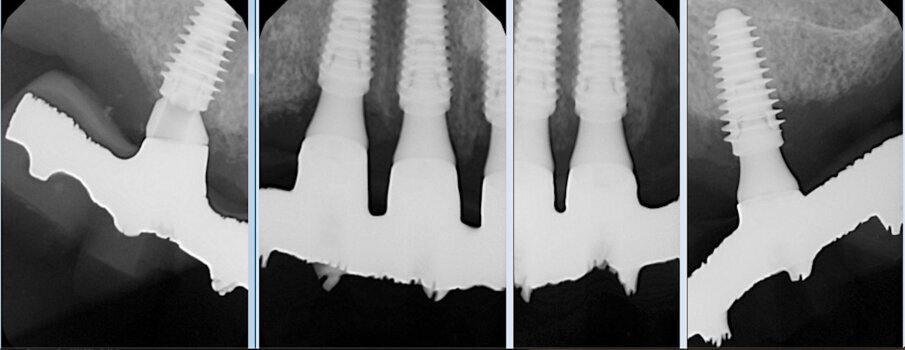

Il risultato finale evidenzia di aver raggiunto l’obbiettivo di ripristinare la funzione ma anche l’estetica in un paziente ancora giovane e motivato a mantenere il manufatto con una più accurata igiene orale (Figg. 9a, 9b). L’esame radiografico eseguito sei mesi dopo l’inserzione della protesi evidenzia la stabilità delle zone innestate precedentemente al posizionamento degli impianti e la precisione delle strutture protesiche (Fig. 10). In una visita di controllo ad un anno dall’inserzione della protesi si può notare il notevole miglioramento estetico prodotto dalla terapia implanto-protesica (Fig. 11).